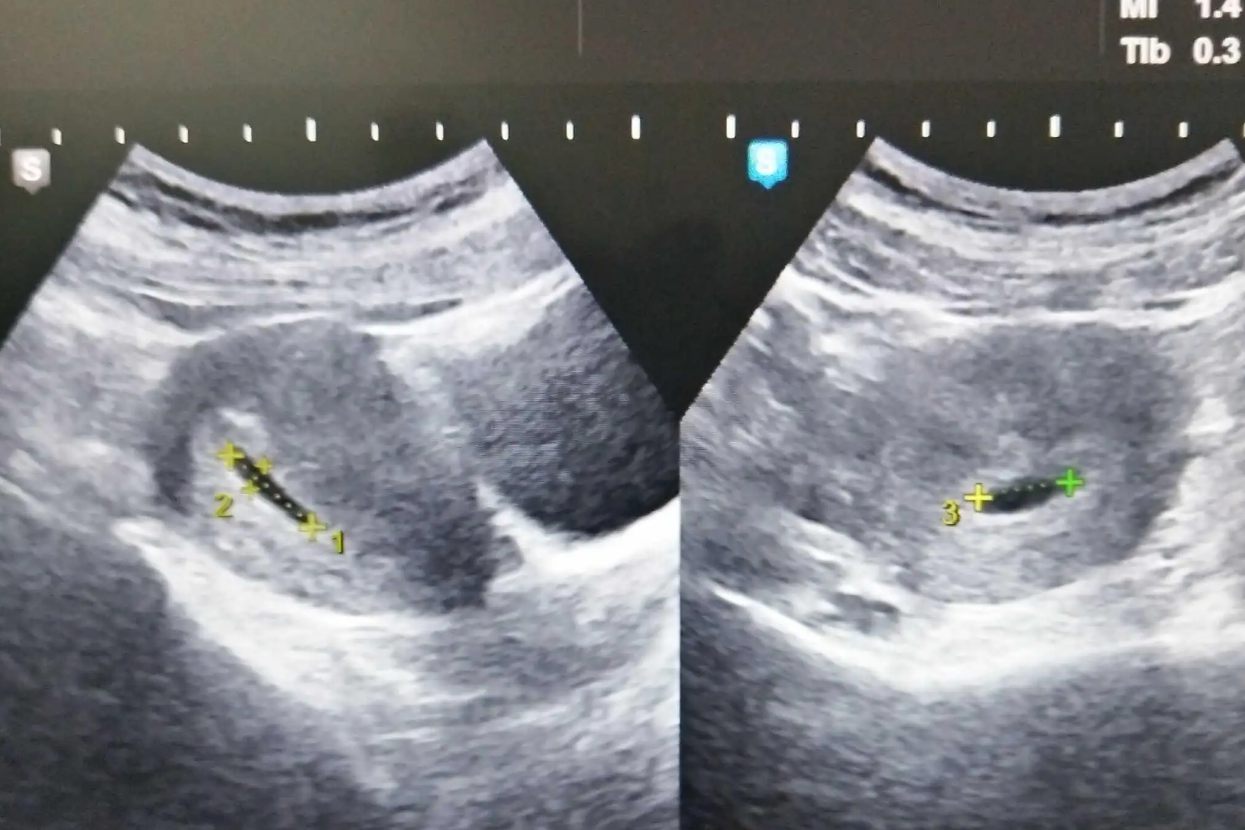

怀孕六周属于孕早期,多数孕妇在进行彩超检查时,可见到胎心、胎芽和原始胎心搏动,但部分排卵较晚,或受精卵着床较晚的孕妇也可能只能见到卵黄囊。

怀孕六周,胎儿约长到0.6厘米左右,重量大约只有3克。多数孕妇在孕6周时,可见到孕囊、胎芽,如果胚胎发育的好,还可以看到心管搏动。

4、 胎儿的神经管也连接到了大脑和脊髓,消化管道开始慢慢成形。B超可见胎囊。